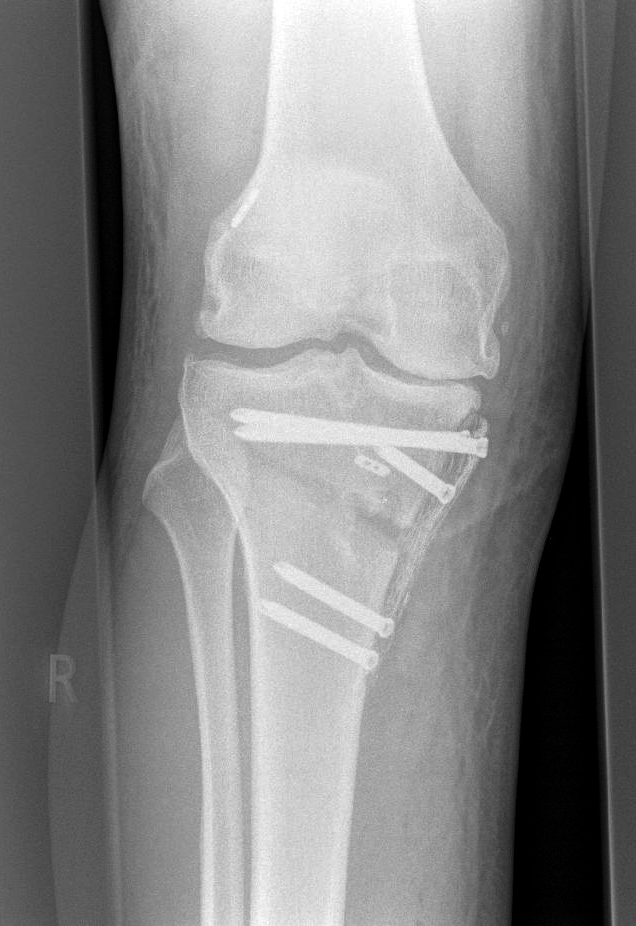

Um die Ausrichtung des Kniegelenks zu verändern, sägt der Operateur teilweise in den Ober- bzw. Unterschenkelknochen hinein und „klappt“ diesen auf, sodass ein Spalt im Knochen entsteht. Mit Hilfe des dadurch erzeugten Winkels kann der Arzt die Fehlstellung ausgleichen. Stabilisiert wird die Korrektur – ähnlich wie nach einem Knochenbruch – durch eine Platte und mehrere Schrauben, die nach sechs bis zwölf Monaten wieder entfernt werden können.

Röntgenbild eines Beines im Kniebereich

Korrigierte O-Beinstellung durch Neuausrichtung des Schienbeins (tibiale Kniegelenknahe Osteotomie)